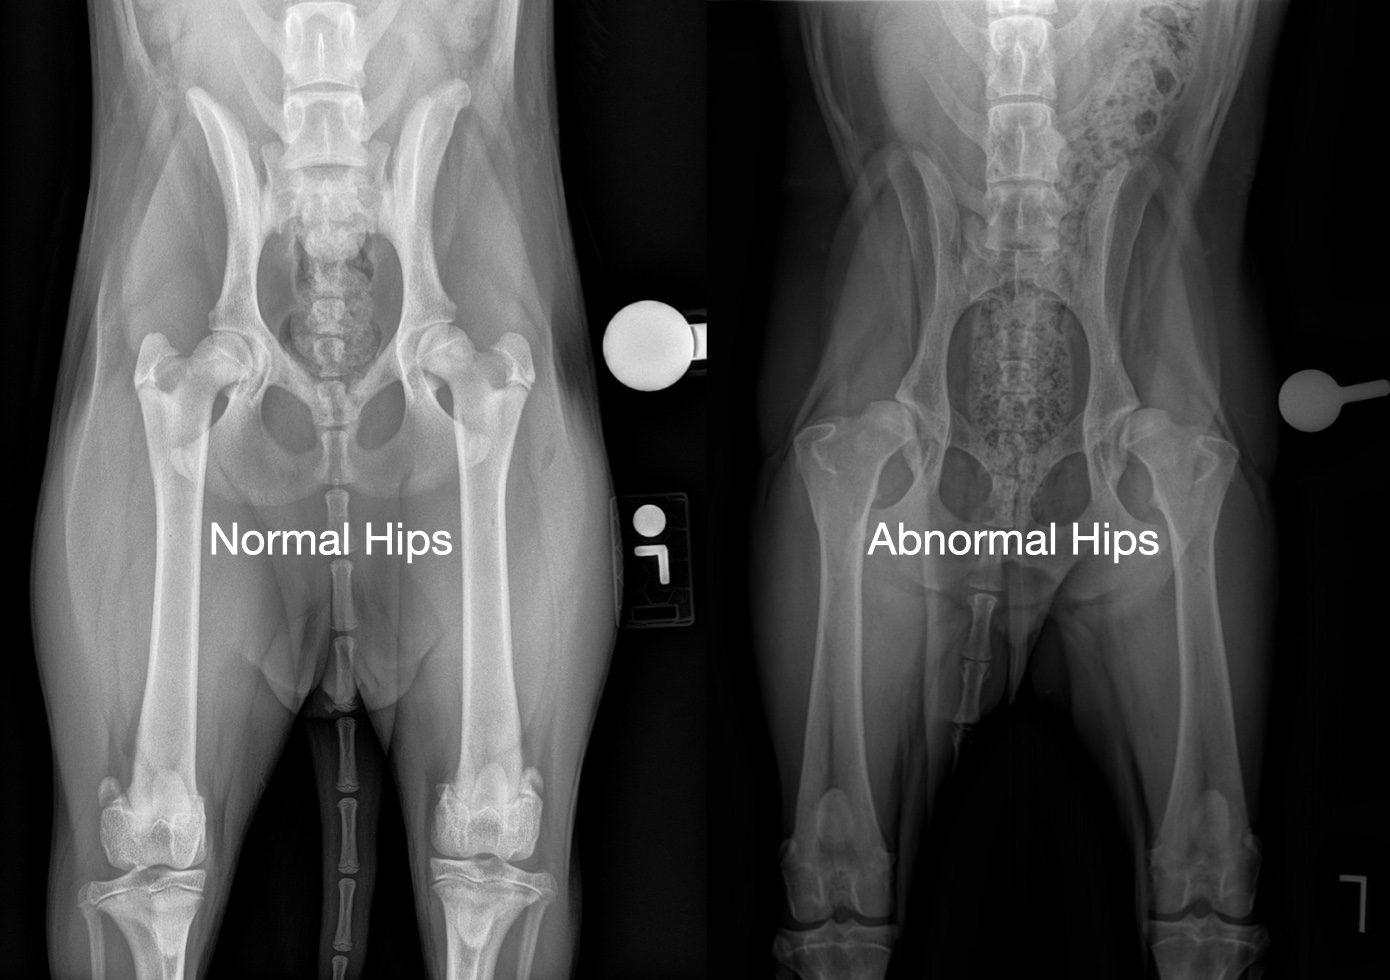

Hip dysplasia, one of the most common orthopedic conditions in dogs, refers to the abnormal formation of the ball-and-socket joint of the hip. When these bones fit together more loosely than they should, the joint has more movement than normal. This looseness (called joint laxity) can lead to instability, osteoarthritis (OA), pain and lameness.